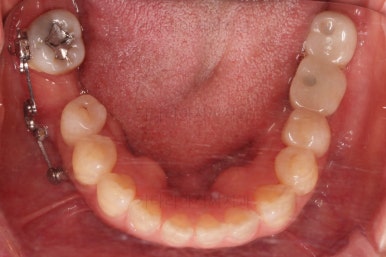

점점 공간이 어금니 크기로 회복되고 있는 것이 보일거에요.

단순히 쓰러진 어금니를 뒤로 밀기만 하는 것이 아니라 안밖의 위치, 회전 양상, 높낮이 등도 정교하게 조절을 합니다.

X-ray 사진으로 중간평가 해주고요.

적절한 자리가 마련되었다고 판단되면 임플란트 식립 가능성을 평가하게 됩니다.

연산동부분교정 9개월 걸렸고요.

이 후에 임플란트 식립부터 치아 머리 완성까지 5개월 가량 걸렸네요.